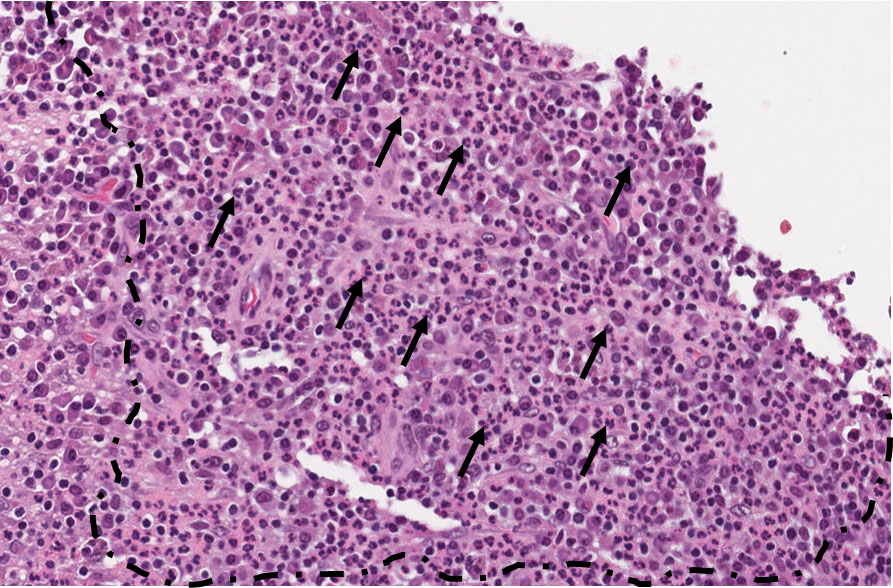

Os cortes histológicos revelam cavidade revestida por epitélio estratificado pavimentoso não ceratinizado. No interior da cavidade e em contato com o epitélio observa-se a supuração (presença de piócitos). Presença de infiltrado inflamatório linfoplasmocitário, vasos de neoformação e cápsula fibrosa na periferia da lesão. Caracterizando tecido de granulação. (Figura 12)

Observar a cavidade (lúmen) (Figura 12) contendo piócitos (pus) circundada por tecido epitelial (Figura 13), linfócitos e plasmócitos (asterisco amarelo – Figura 14) no tecido conjuntivo, e a cápsula fibrosa onde observamos também angiogênese (asterisco verde – Figura 14).

Cisto Abscedado